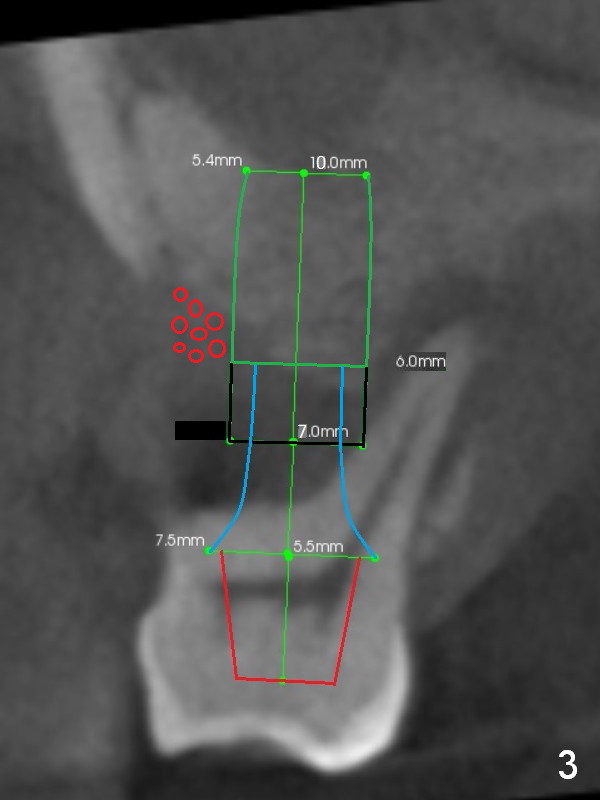

A safe method is to use a shorter implant and place it as deep as possible so that the majority of the threads are subcrestal (Fig.3 green). Pack bone graft tightly (smaller red circles) and also check whether there is a piece of gauze in the socket prior to grafting. The corresponding changes are to place a long abutment with long cuff (7.5x7(5) mm). Bone density is relatively low. Prepare bone expanders.